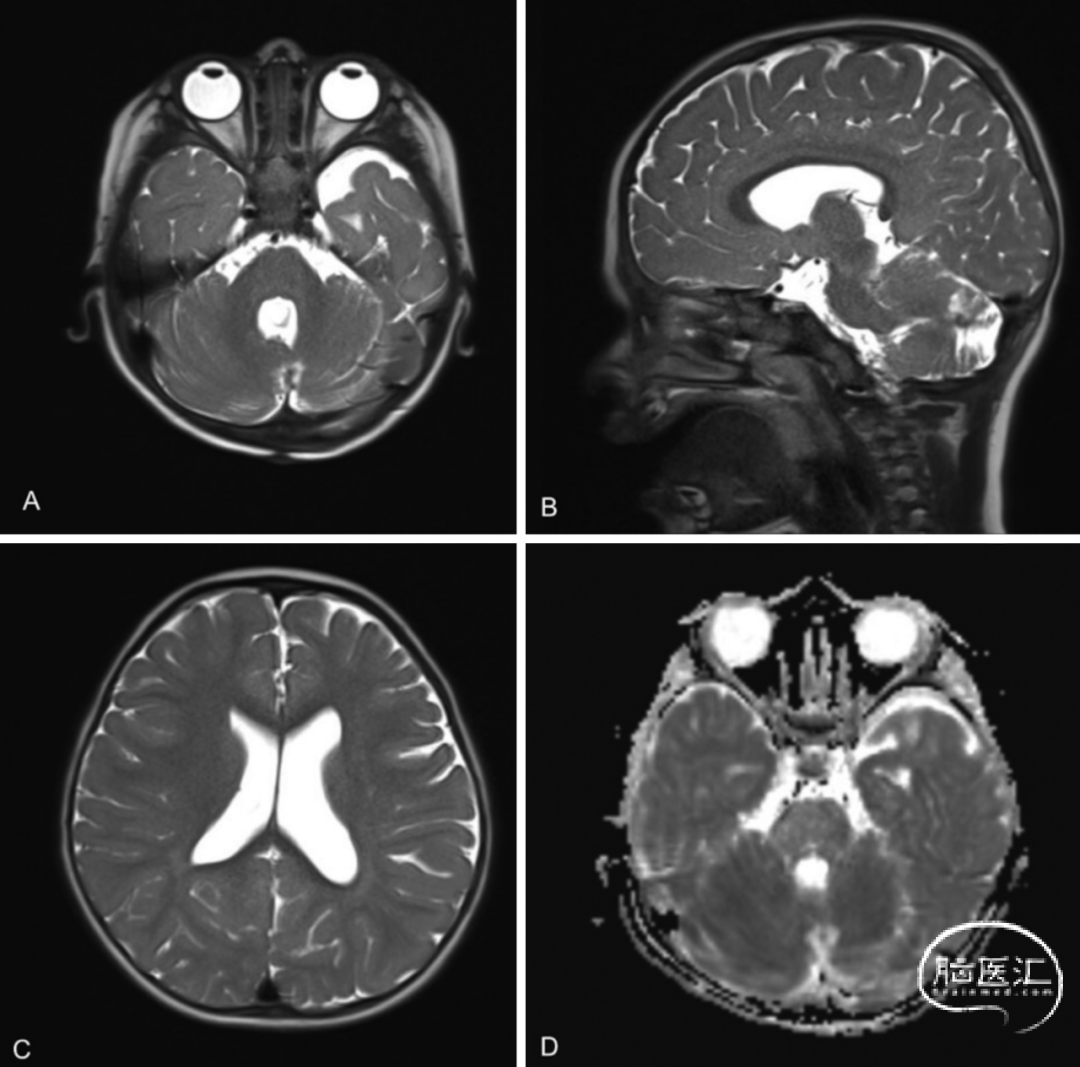

● 术后患者恢复顺利(图4)。给予地塞米松控制水肿。患者出现短暂恶心、呕吐,3天后症状缓解并出院。最终病理报告确认切除的肿块为复发性皮样囊肿,无感染。术后1个月随访时,患者运动功能恢复至术前水平,恢复良好。术后3个月MRI随访显示无残留皮样囊肿,梗阻性脑积水完全缓解(图5)。

图5. 随访MRI检查显示切除腔缩小,脑室扩大情况得到缓解,与术前相比弥散受限减轻。